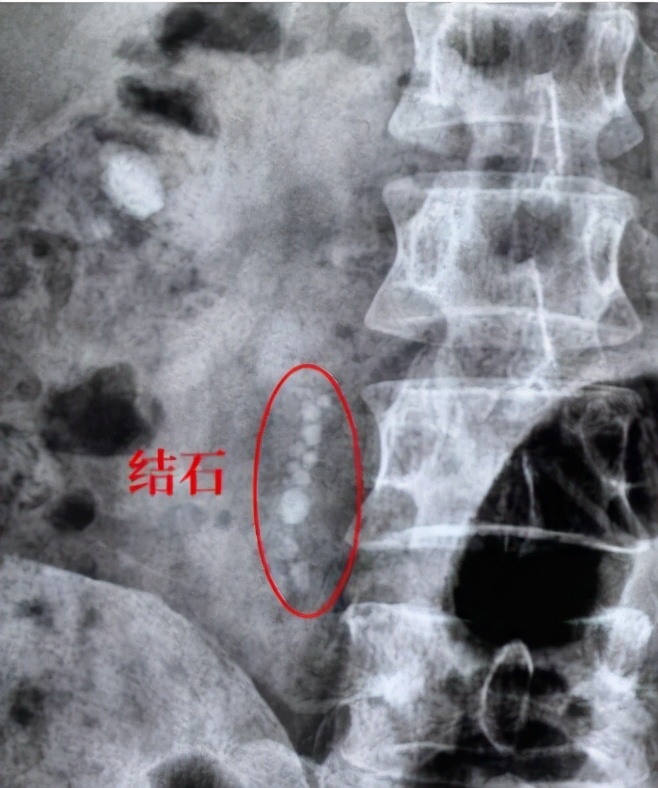

体外冲击波碎石术后,因碎石无法排出,堵在输尿管里,形成石街,导致输尿管梗阻,引起肾积水,需进一步治疗